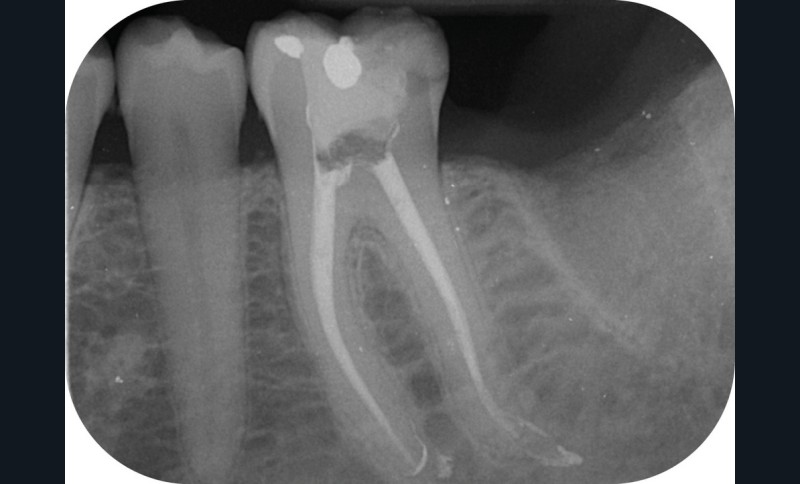

Au moment de la rédaction de ce document, dix-huit systèmes de mise en forme canalaire sont commercialisés sur le marché français. Toutes les publicités promeuvent des améliorations de l’efficacité, de la souplesse et surtout de la résistance à la fracture (fig. 2). Il faut reconnaître que même si ces systèmes sont très différents, les résultats obtenus sont finalement assez constants, et il faudrait des études très poussées pour démontrer la supériorité de l’un par rapport à l’autre (si tant est qu’il y en ait une !).

Parmi les reproches faits à ces systèmes de préparation canalaire, le risque de fracture est celui qui est le plus avancé. Et quelle frustration pour le praticien lorsqu’elle…